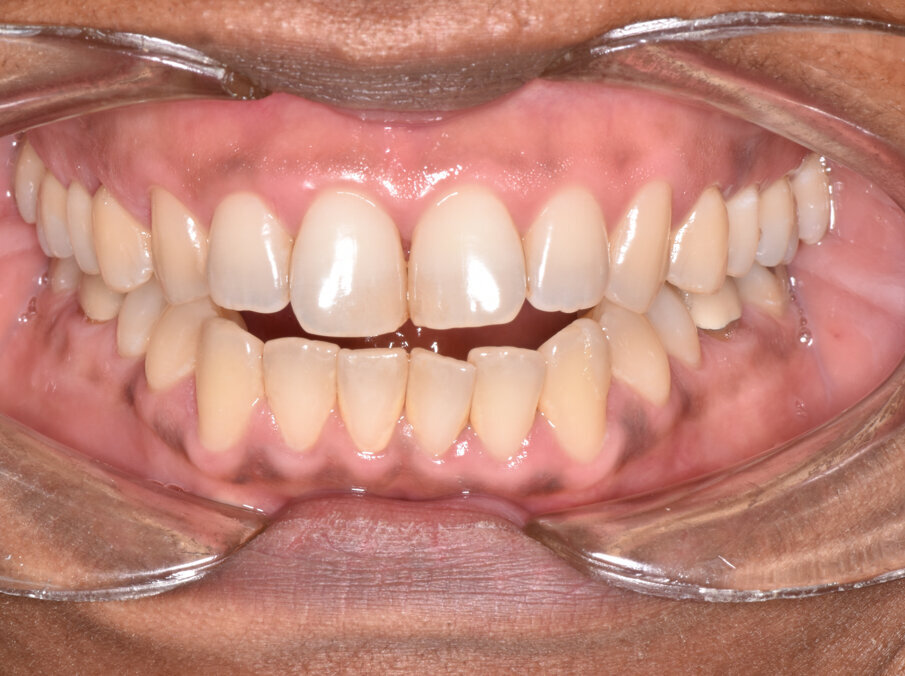

A 56-year-old female patient presented with a Class III malocclusion, anterior crowding and a 2-3 mm anterior open bite. Clinical photographs showed an ideal incisor display upon smiling. The panoramic film was unremarkable, and the lateral cephalometric film revealed a negative 1 mm overjet. (Figs. 1 to 10)

The 31-aligner Spark treatment concluded in five appointments over 7.75 months of active treatment without the need for TADS or refinement aligners. The patient’s excellent compliance was an important factor in the results achieved. Post-treatment photographs demonstrate correction of her Class III, crowded, anterior open bite malocclusion. (Figs. 16-23)